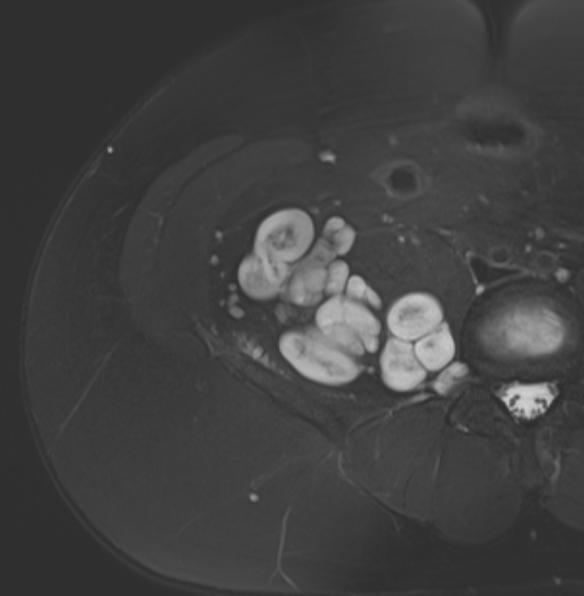

Neurofibroma median nerve

Target sign

- hypointense centrally

- hyperintense peripherally